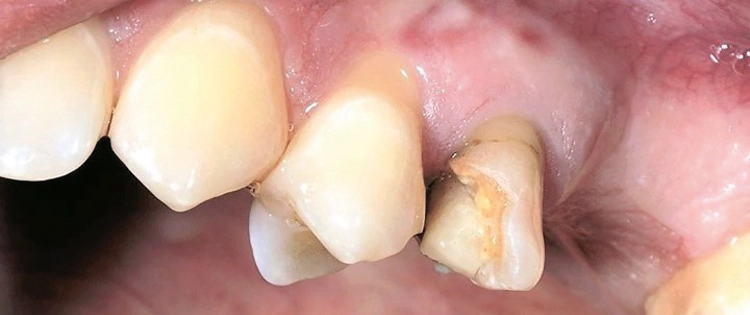

Nach der Pilotbohrung wird das Implantatbett mit Condensern in aufsteigenden Durchmessern aufbereitet. Erreicht man mit einem Condenser „handfest“ eine Stabilität von 20 Ncm, so wird ein Implantat mit dem nächstgrößeren Durchmesser inseriert. Die Bilder (Abbildungen 4a-h) zeigen das Beispiel einer Sofortimplantation regio 16.

Dr. Volker Knorr, Eislingen

Es wurde ein Champions (R)Evolution-Implantat ø 4,5 mm – L 8 mm in Verbindung mit einem internen, direkten Sinuslift (IDS) inseriert. Mit dem Condenser ø 3,8 mm wurden „handfest“ (etwa 20 Ncm) erreicht und deshalb ein Implantat ø 4,0 mm inseriert. Hätte man die Stabilität erst mit dem Condenser ø 5,3 mm erreicht, so hätte man ein Champions (R)Evolution-Implantat gleicher Länge, aber mit dem Durchmesser 5,5 mm einsetzen sollen.